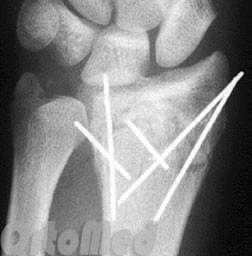

Закрытая репозиция и чрескожная фиксация спицами

Была популярна на протяжении многих лет и продолжает оставаться одним из самых популярных методов в международном масштабе.

Сначала врач закрыто устраняет смещение отломков, затем через отломки в определенных (учитывая характер перелома) направлениях просверливаются спицы.

Плюсы: малая травматичность, быстрота, легкость, дешевизна, отсутствие разреза и как следствие послеоперационного рубца

Минусы: невозможность начала ранней разработки лучезапястного сустава, вследствие чего риск возникновения необратимой контрактуры (отсутствие движений в суставе).